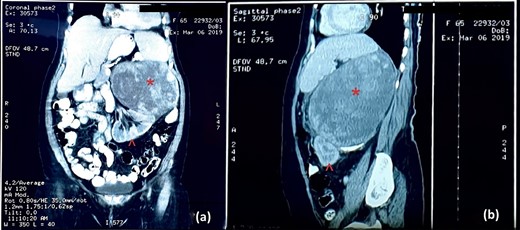

An abdominal ultrasound (US) revealed a 12 × 12 cm solid mass from the left suprarenal area (Fig. 1). Contrasted computed tomography (CT) revealed a 17.5 × 11.5 cm enhancing lesion in the left suprarenal region, completely replacing the left adrenal gland. The left kidney was inferiorly displaced, and coarse calcification was seen at the lesion’s periphery without lymph node enlargement. The contralateral adrenal gland, retroperitoneal and peritoneal structures were normal (Figs 2 and 3). Screening for primary carcinomas presenting as adrenal deposits utilizing clinical examination, pan endoscopy and contrasted CT were all negative. At this point, our working diagnosis was non-secreting left pheochromocytoma, and elective laparoscopic left adrenalectomy was planned.

Cross-sectional image of computer tomogram; (a) non-contrasted image and (b) contrasted image; the red asterisk mark in (a, b) shows the tumour, the red arrowhead in (a) shows anteriorly displaced pancreas and the red arrowhead in (b) shows the clear distinction of tumour from the left psoas.